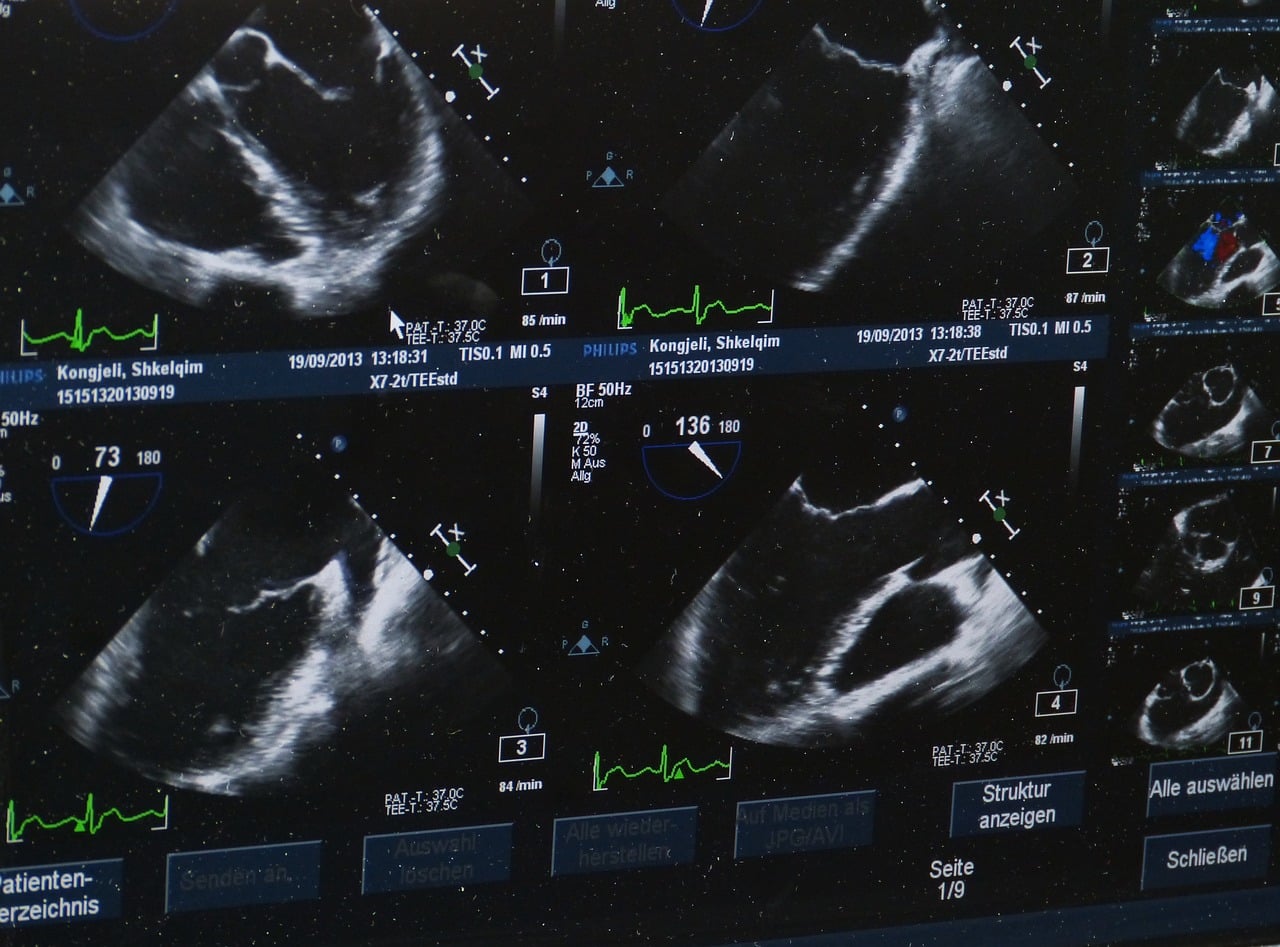

Si cette malformation congénitale est le plus souvent observée pour la première fois lors d’une échographie prénatale, avant d’être définitivement diagnostiquée par IRM à la fin du deuxième ou du troisième trimestre de la grossesse, les interventions chirurgicales s’opéraient jusqu’à présent après la naissance.

Récemment, des médecins du Boston Children’s Hospital et du Brigham and Women’s Hospital ont cependant tenté et réussi une embolisation in utero sur un fœtus âgé de 34 semaines et 2 jours d’âge gestationnel, guidés par des ultrasons. Cette grande première a été réalisée sous la supervision de la FDA (Food and Drug Administration).

En raison d’une rupture prématurée des membranes lors de l’embolisation in utero, le nourrisson a dû naître par induction du travail (en utilisant une stimulation des contractions utérines) deux jours plus tard. Cependant, l’échocardiographie a montré une normalisation progressive du débit cardiaque. Le nouveau-né n’a donc pas eu besoin d’assistance cardiovasculaire ni de chirurgie suite au traitement in utero. Il a ensuite été surveillé pendant plusieurs semaines en raison de sa prématurité. Pendant ce laps de temps, les médecins n’ont constaté aucun déclin agressif habituellement observé généralement après la naissance.